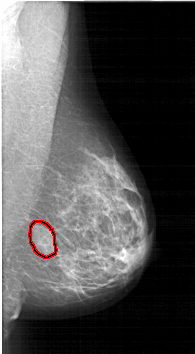

A_1764_1.LEFT_MLO

LEFT_MLO LINES 5971 PIXELS_PER_LINE 3496 BITS_PER_PIXEL 12 RESOLUTION 43.5 NON_OVERLAY

FILE: A_1764_1.RIGHT_MLO.OVERLAY

TOTAL_ABNORMALITIES 1

ABNORMALITY 1

LESION_TYPE MASS SHAPE OVAL MARGINS ILL_DEFINED

ASSESSMENT 4

SUBTLETY 4

PATHOLOGY BENIGN

TOTAL_OUTLINES 1

BOUNDARY